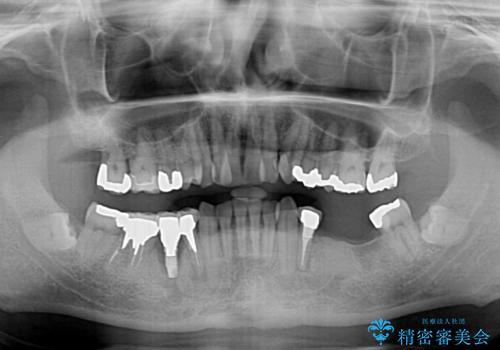

奥歯の欠損と前歯のデコボコを治したい インプラントと矯正治療の総合歯科治療

- 下顎両側の欠損と上顎前歯のデコボコを気にして来院された患者様です。

デコボコは今まで気にせずにいたそうですが、奥歯の欠損改善を機に、矯正治療に興味があるので、相談したいとのことでした。

奥歯に欠損が多く、矯正治療はやや難航することが予想されますが、患者様の希望もあり、上顎左右小臼歯を1本ずつ抜歯し、ワイヤー装置にて矯正治療を行うこととしました。

矯正歯科治療を行うに当たり、痛みや違和感を感じている歯の根管治療を行い、矯正治療中にインプラント埋入し、補綴治療と矯正治療を同時に終了できるように進めて行くこととしました。

銀歯やむし歯治療されている歯を抜歯する治療計画としたため、やや時間はかかりましたが、治療後の仕上がりには大変満足していただけました。